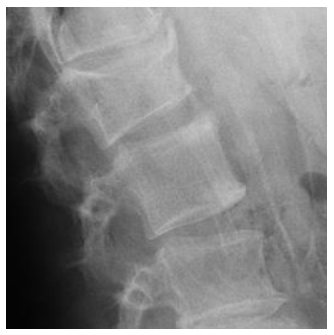

Morphometric fracture was related to radiographic progression. Although it may be surprising that more than 25% of our patients had a morphometric fracture, a previous study found 40% to have vertebral fractures with a higher fracture rate in patients with PsAax than in patients with spondylitis [28]. In patients with spondylitis, the presence of a fracture has been related to greater radiographic damage [29,30]. This fact could be secondary to two reasons: the first one, to the fact that axial immobility associated with radiographic damage would limit the patient's mobility and thereby influence bone fragility. However, it is necessary that other factors intervene in this association because the increase in radiographic progression may not have a significant influence on the mobility of the patient. The second reason, the presence of the syndesmophyte could change different biomechanical parameters that would decrease the resistance of the bone and with it an increase in the presence of fracture. In these cases, the sequence would begin in the syndemophyte and end in the vertebral fracture. We found an inverse relationship: radiographic damage was secondary to the morphometric fracture. Furthermore, individual analysis of the patients showed that some of the vertebrae that were fractured were those that had posterior radiographic progression (Figure 1 and Figure 2). We hypothesize that microtrauma would cause microfractures that would trigger the activation of progenitor cells and their transformation into osteoblasts mediated by bone morphogenetic protein (BMP); thus, the post-fracture remodelling process could participate in the formation of the syndesmophyte [31].